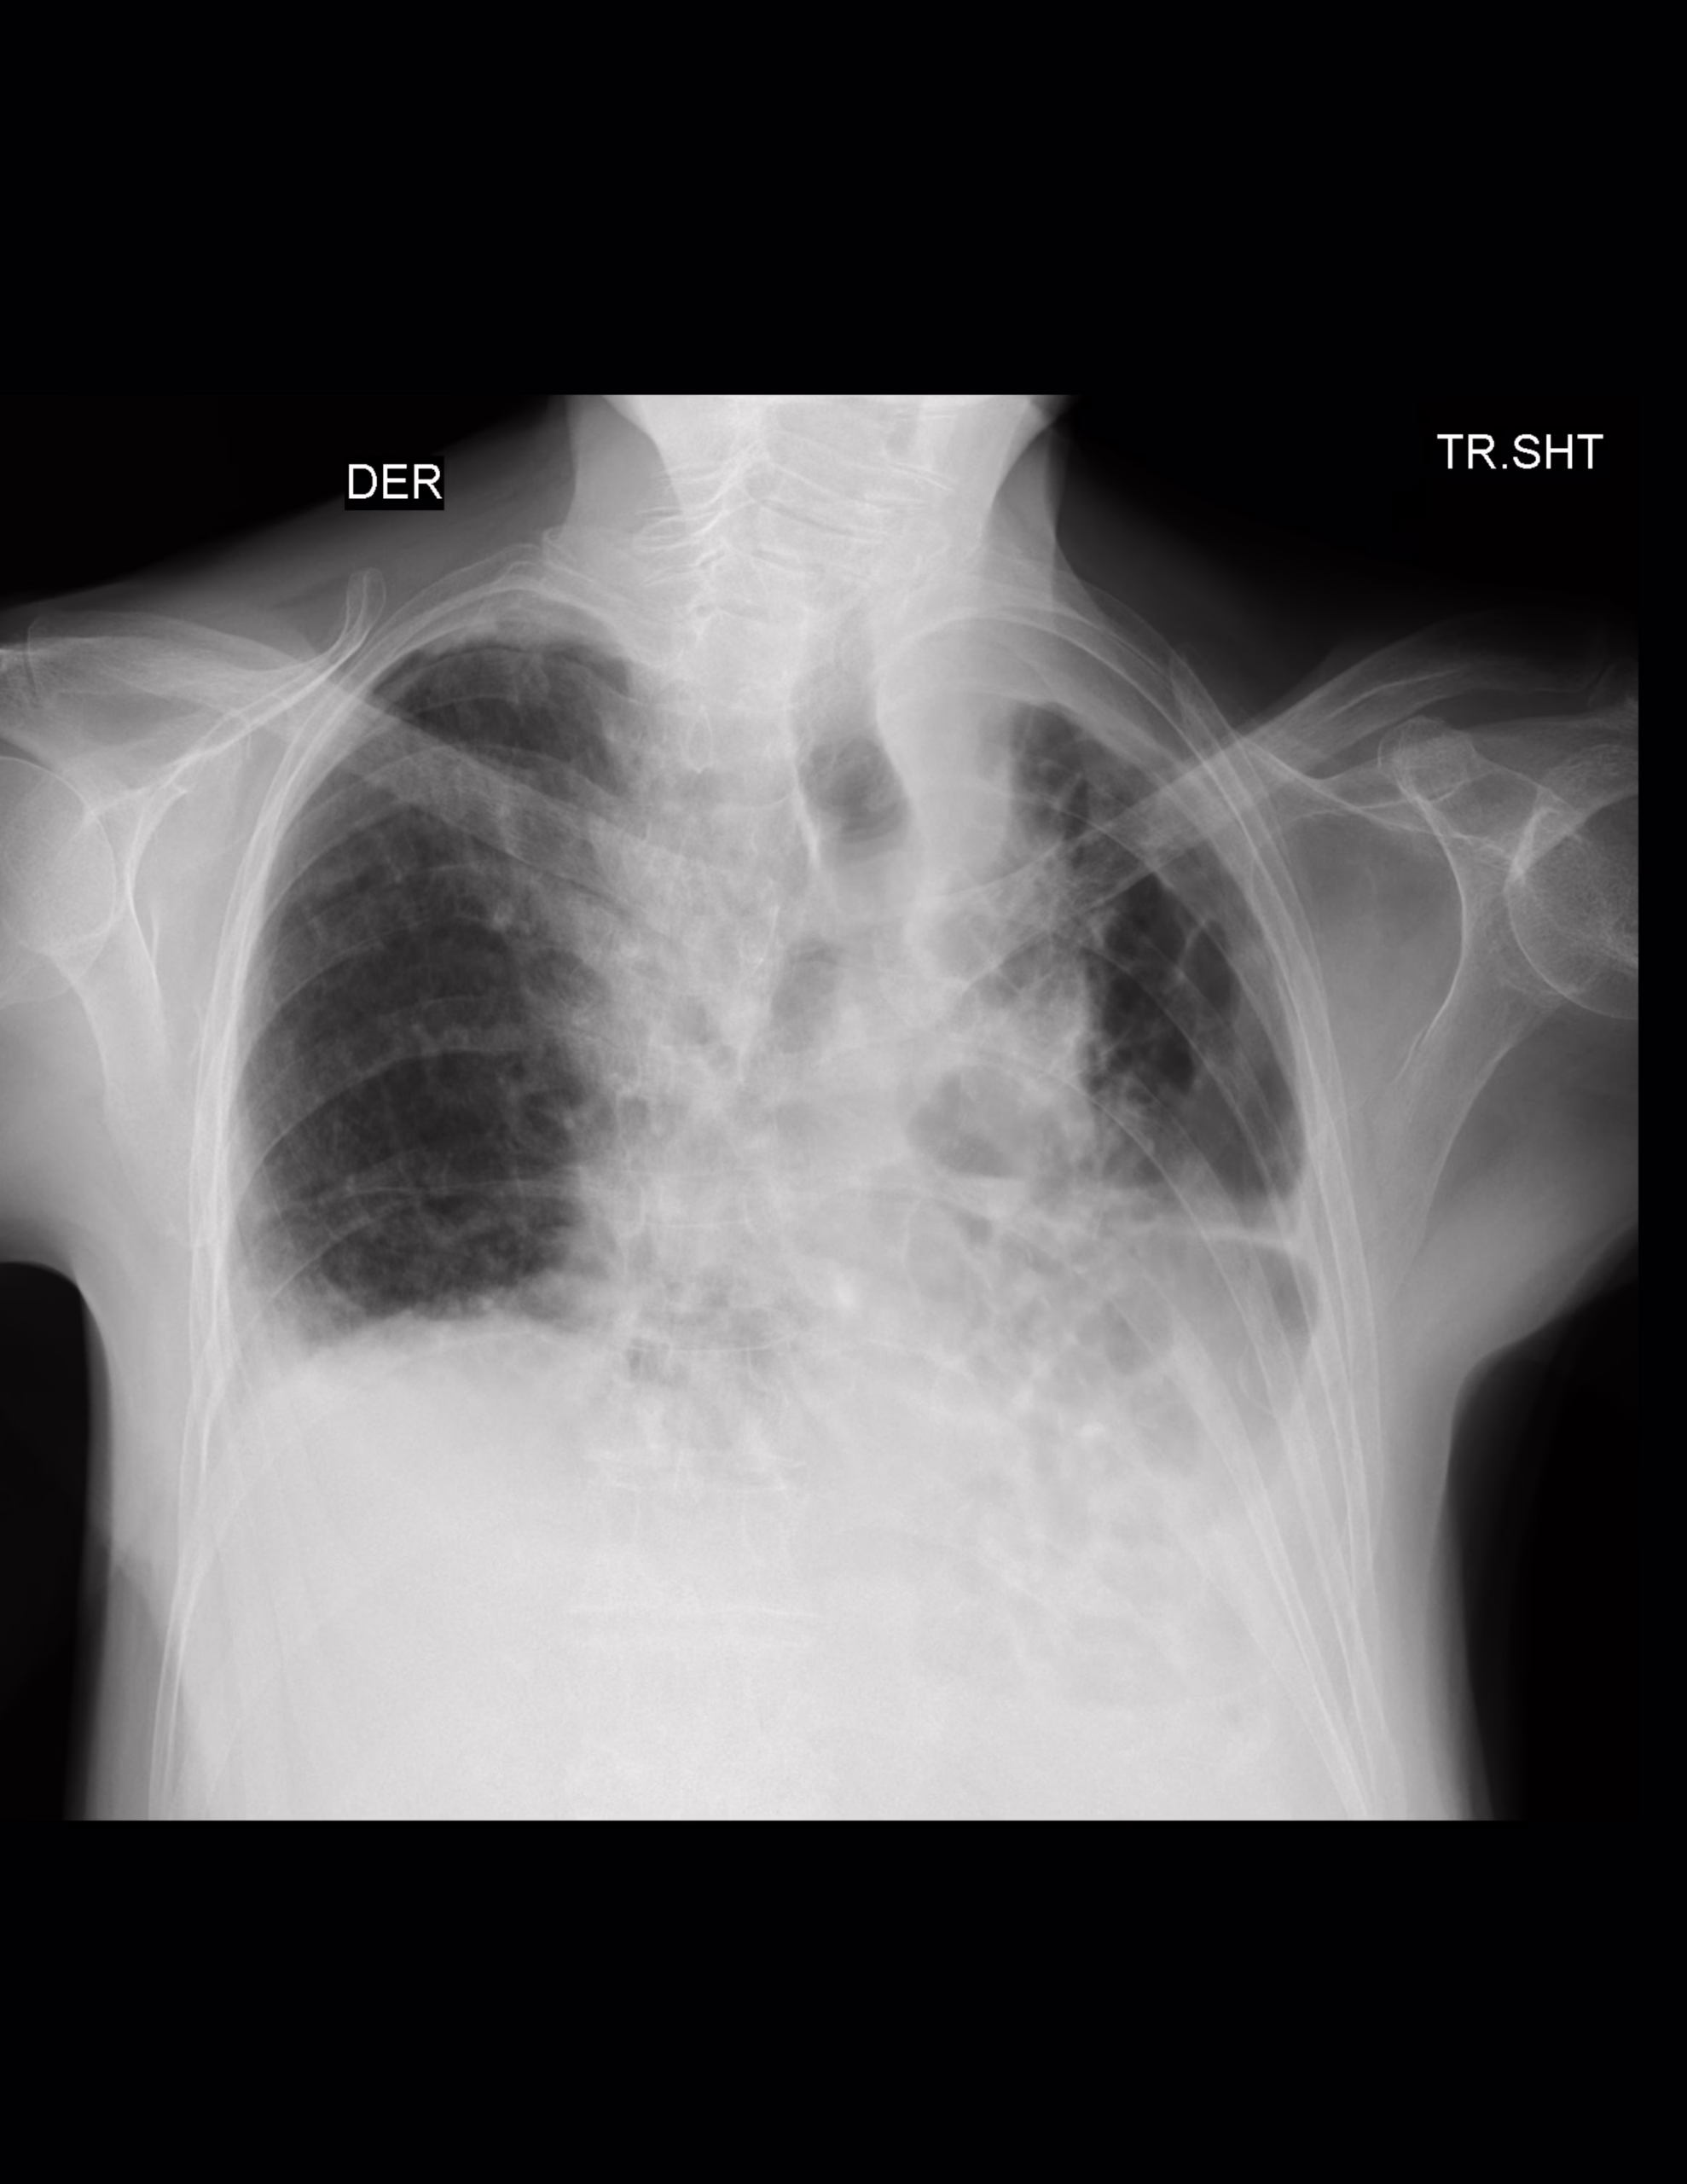

LA PROYECCION RADIOLOGICA OBTENIDA NOS MUESTRA LOS SIGUIENTES HALLAZGOS:

-Tejidos blandos, simétricos, con adecuada densidad, sin evidencia alteraciones.

-Estructuras óseas, sin evidencia de lesiones líticas, blásticas o perdida de la contigüidad. Existen osteofitos marginales.

-Vía aérea permeable, con desviación hacia la izquierda. Botón aórtico con calcificaciones.

-Mediastino, con aparente aumento sus diámetros.

-Corazón, central, con índice cardiotorácico de 0.51.

-Hilios pulmonares, no se observan

-Trama bronco-vascular, con alteración.

-Campos pulmonares, con opacidad reticular difusa. Así como atelectasias subpleurales distribución aleatoria periférica de predominio en pulmón izquierdo, que disminuye en el volumen de parénquima pulmonar izquierdo

-Existe ascenso de hemidiafragma izquierdo, propiamente asociado a atelectasias.

OPINIÓN RADIOLÓGICA:

EN EL PRESENTE ESTUDIO RADIOGRÁFICO, EXISTE NEUMOPATÍA CRÓNICA INTERSTICIAL DE PREDOMINIO IZQUIERDO, CON DISMINUCIÓN DEL VOLUMEN PULMONAR IZQUIERDO CON ASCENSO DEL HEMIDIAFRAGMA Y DICEN DE LA TRÁQUEA.

ATEROESCLEROSIS.

CAMBIOS OSTEODEGENERATIVOS.